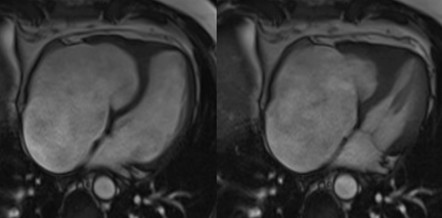

We report the case of a 48-year-old male with chronic eosinophilic leukaemia (CEL) complicated by multiorgan damage, including chronic kidney disease (CKD) and liver disease with recurrent ascites. Cardiac follow-up began at CEL diagnosis. The patient remained stable until 2015, when he underwent two atrial tachycardia ablations. Cardiac magnetic resonance imaging suggested Loeffler endocarditis, showing right ventricle (RV) fibrosis, mildly impaired RV systolic function and severe tricuspid regurgitation (TR). The left ventricle (LV) remained preserved. Cardiac computed tomography excluded coronary disease. In June 2025, despite guideline-directed medical therapy, the patient developed severe dyspnea, massive ascites and acute kidney injury on CKD. Transthoracic (TTE) and transoesophageal echocardiography showed torrential TR not amenable to percutaneous repair. Laboratory results showed normal blood count, serum creatinine 5.5 mg/dL, bilirubin 2 mg/dL, NT-proBNP 7950 pg/mL. Electrocardiography showed junctional rhythm. On admission, intravenous furosemide was continued. A 5-L paracentesis yielded negative cytology and microbiology. TTE confirmed severely dilated RV and atrium, paradoxical septal motion, hypokinetic RV and torrential TR. LV function was normal. Right heart catheterization revealed reduced cardiac index (2.04 L/min/m²), mildly elevated pulmonary capillary wedge pressure (14 mmHg), normal pulmonary pressures (24/15/19 mmHg), normal pulmonary vascular resistance (1.3 WU) and elevated right atrial pressure (19 mmHg). Low dose dopamine (2 mcg/kg/min) improved perfusion and diuresis, leading to clinical stabilization with weight loss (−19 kg), waist reduction (−11 cm), and improved labs. Multisystem evaluation was undertaken. Portal hypertension and decompensated liver disease were excluded. Liver biopsy revealed extensive fibrosis without cirrhosis or malignancy. MELD-XI was 48. Haematology confirmed longstanding CEL remission. Imatinib was discontinued, with monthly molecular monitoring. Renal function normalized under inotropes, with no further tests needed. Extracardiac and serologic workup was negative. Blood type: B Rh+. The case was reviewed by the transplant team. No absolute contraindications to heart transplantation were found. Combined heart–liver transplantation was deemed unnecessary given the absence of cirrhosis. LVAD was excluded. On August 1st, 2025, the patient was listed for urgent heart transplantation (Urgency level 2).